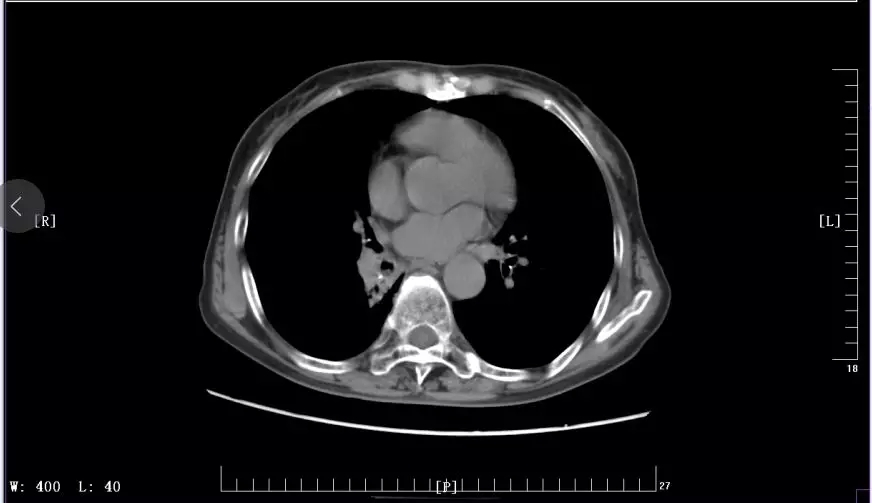

下圖是徐麗參加KEYNOTE-407臨床試驗(yàn)前后CT影像對(duì)比圖:

2018年6月治療中CT影像